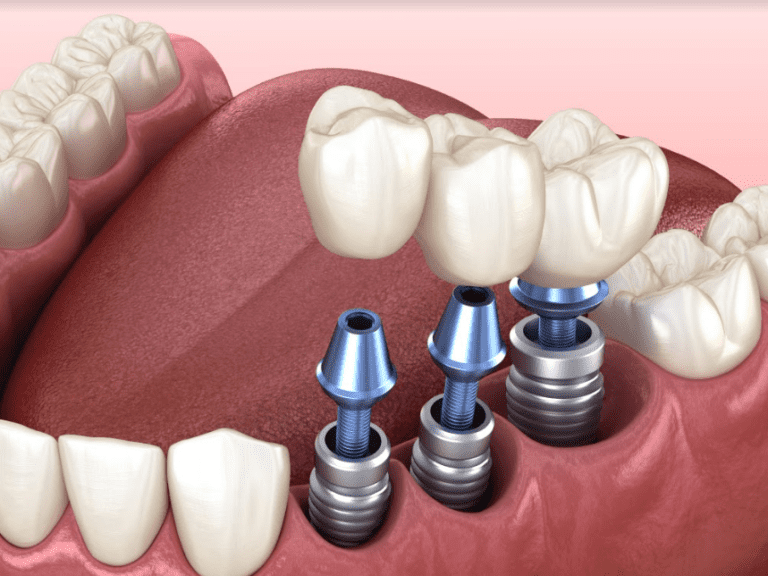

تم اختراع زراعة الأسنان كما تُعرف بشكلها اليوم عام 1952 من قبل جراح العظام السويدي المسمى «بيرينجفار برينمارك»؛ والذي يُعرف بـ«أبو زراعة الأسنان الحديثة». إن زراعة الأسنان عبارة عن أداة جراحية توضع في عظم الفك وتُترك لتندمج مع العظم على مدى بضعة أشهر. تعمل زراعة الأسنان كبديل لجذر السن المفقود. في المقابل، يعمل جذر السن الاصطناعي المزروع على تثبيت سن أو جسر بديل. كما أن وجود غرسة أسنان مدمجة في عظم الفك هي أقرب شيء لتقليد الأسنان الطبيعية، ذلك لأنها تقف من تلقاء نفسها دون التأثير على الأسنان المجاورة وتتمتع بثبات كبير. تسمى عملية الدمج بين زراعة الأسنان وعظم الفك بالـ«الاندماج العظمي». وتُصنع معظم عمليات زرع الأسنان من التيتانيوم، مما يسمح لها بالاندماج مع العظام دون التعرف عليها كجسم غريب في الجسم.

غرسات الأسنان هي أكثر أنواع زراعة الأسنان شيوعاً والمناسبة لمعظم المرضى، لكنها تحتاج إلى عظم فك جيد وصحي حتى تندمج فيه بشكلٍ صحيح. وهي عناصر نابيّة على شكل مسامير. توضع في الفك الذي يتم تركيب الأسنان الاصطناعية عليه.

بمجرد الانتهاء من العملية، يستغرق الأمر بعض الوقت للشفاء. إنها تتطلب وقتاً للاندماج معاً وإنشاء بنية متماسكة. وبمجرد أن تلتئم، يمكن وضع الأسنان الاصطناعية في فجوتها المخصصة لتتناسب مع الأسنان المحيطة. وإذا لم تبدو فكرة وضع شيء ما في عظم الفك مستساغة، يمكن اللجوء إلى ثاني أكثر عمليات الزرع شيوعاً.

بمجرد وجود عظم قوي وكاف، يصبح المكان جاهزاً للزرع. وفي موعد وضع الغرسة، يتم وضع غرسة الأسنان -عمود التيتانيوم- في العظام باستخدام أدوات خاصة. ثم يتم وضع ما يسمى بـ«غطاء الشفاء» فوق الغرسة، ويتم خياطة اللثة، وتبدأ مرحلة الشفاء. كما يمكن خلال مرحلة الشفاء هذه تركيب طقم أسنان مؤقت لاستبدال الأسنان المفقودة لأغراض تجميلية.

بعد انقضاء فترة الشفاء المطلوبة، يتم اختبار الأسنان المزروعة لتحديد ما إذا كان قد تم التحامها بنجاح مع العظام المحيطة. وبمجرد تأكيد ذلك، يتم توصيل مكوّن اصطناعي بغرسة الأسنان عبر برغي. يسمى هذا المكون بالدعامة. ومهمّته الاحتفاظ بالسن البديل أو «التاج». بعدها يأخذ طبيب الأسنان انطباعاً -قالباً- عن هذه الدعامة في الفم، ويكون تاج السن المزروع مصنوعاً حسب الطلب. يتم تثبيت تاج الغرسة على الدعامة بواسطة اللصق أو البرغي.